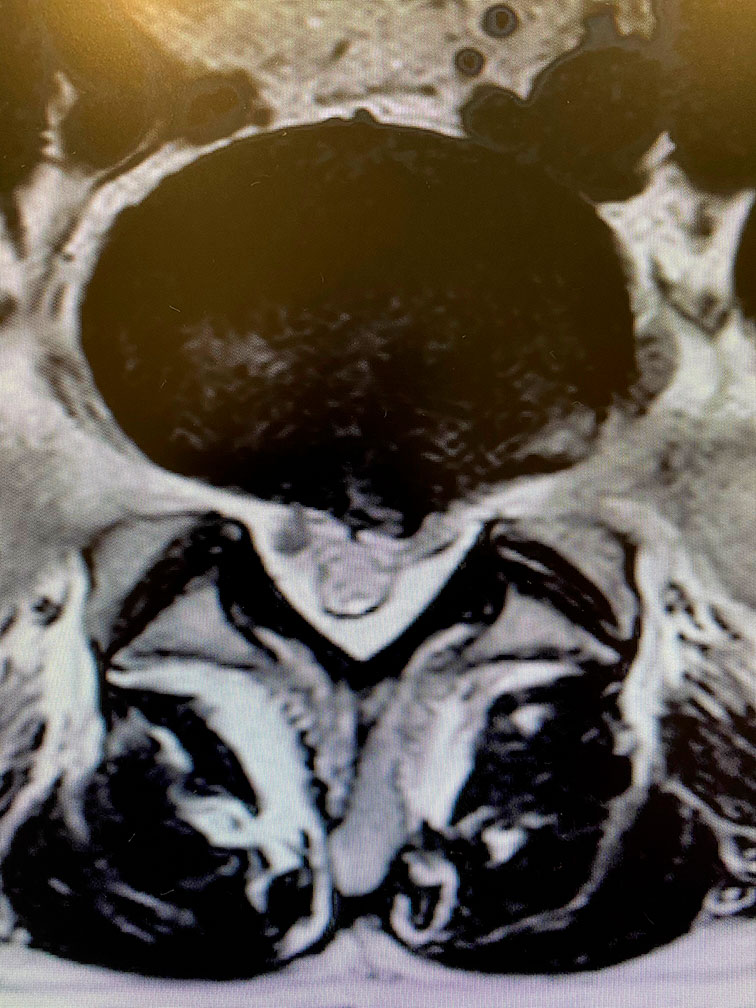

Estos dolores están provocados por una compresión de la raíz pasante y saliente entre la vértebra lumbar 5 y el sacro.

Se realiza una incisión de 3 milímetros entre la  5º vértebra lumbar y el sacro y se realiza un vaciado en la zona de fibrosis para liberar la raíz completamente.

Se realiza una disección de la raíz L5 y posteriormente una movilización de la misma para identificar la hernia.

Posteriormente utilizando coagulación para evitar que la sangre dificulte el proceso, se procede a la extracción de la hernia y material discal.